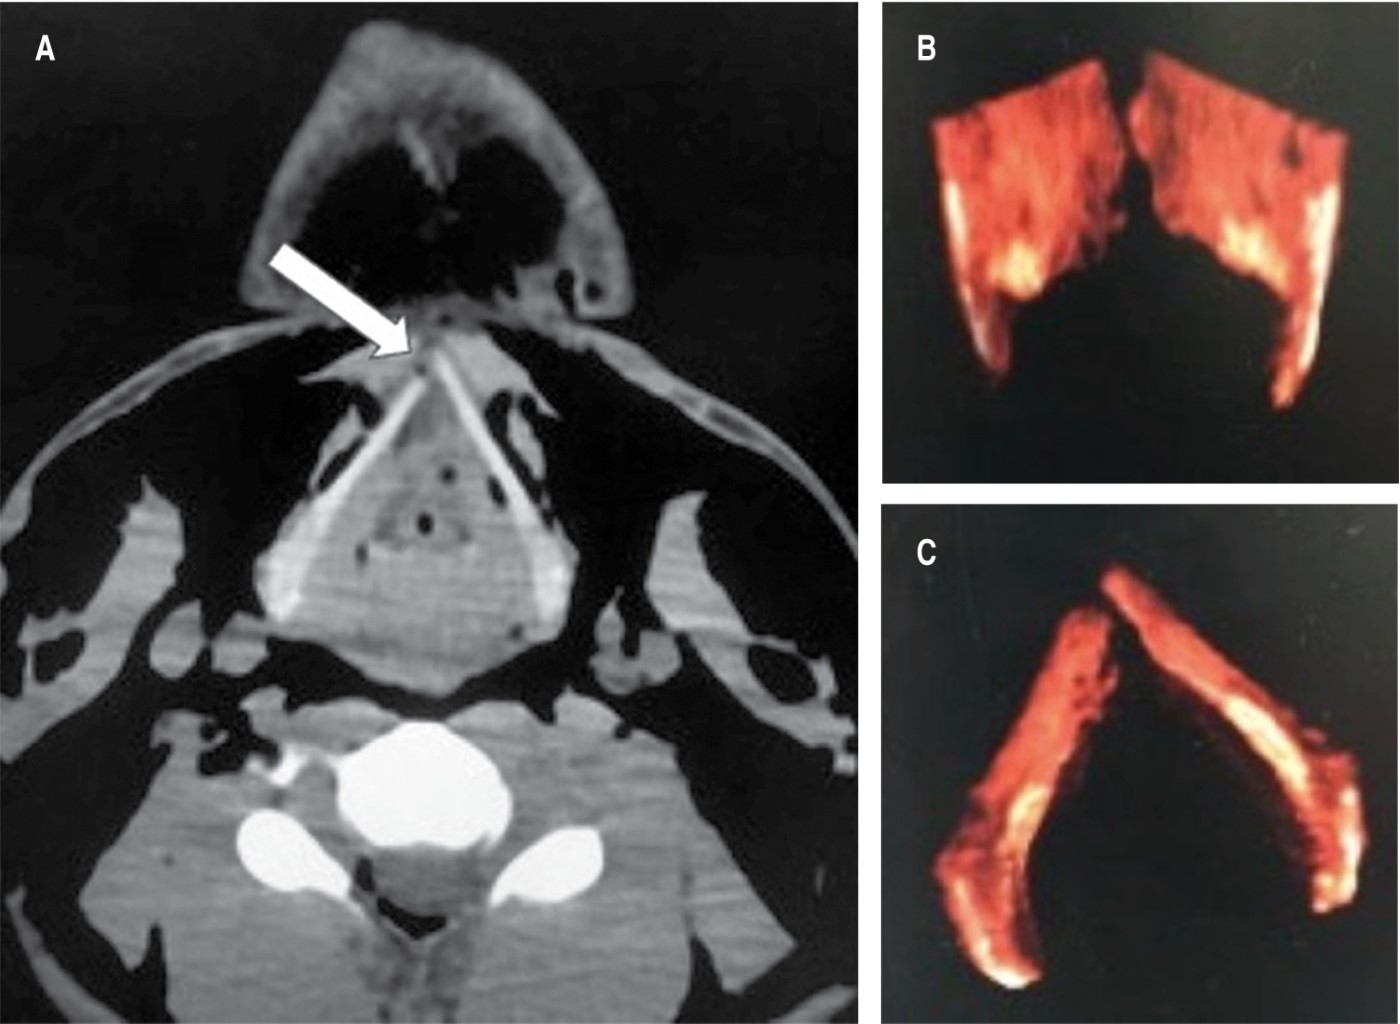

En seguida el paciente fue trasladado para la realización de tomografía computarizada, cuyas imágenes mostraron enfisema subcutáneo en cuello desde el mentón hasta las clavículas y esternón, incluso en mediastino; también se pudo documentar fractura del cartílago tiroides y mediante reconstrucción 3D se demostró un trazo de fractura longitudinal que separó ambas láminas cuadrangulares (Figura 3).

Figura 3